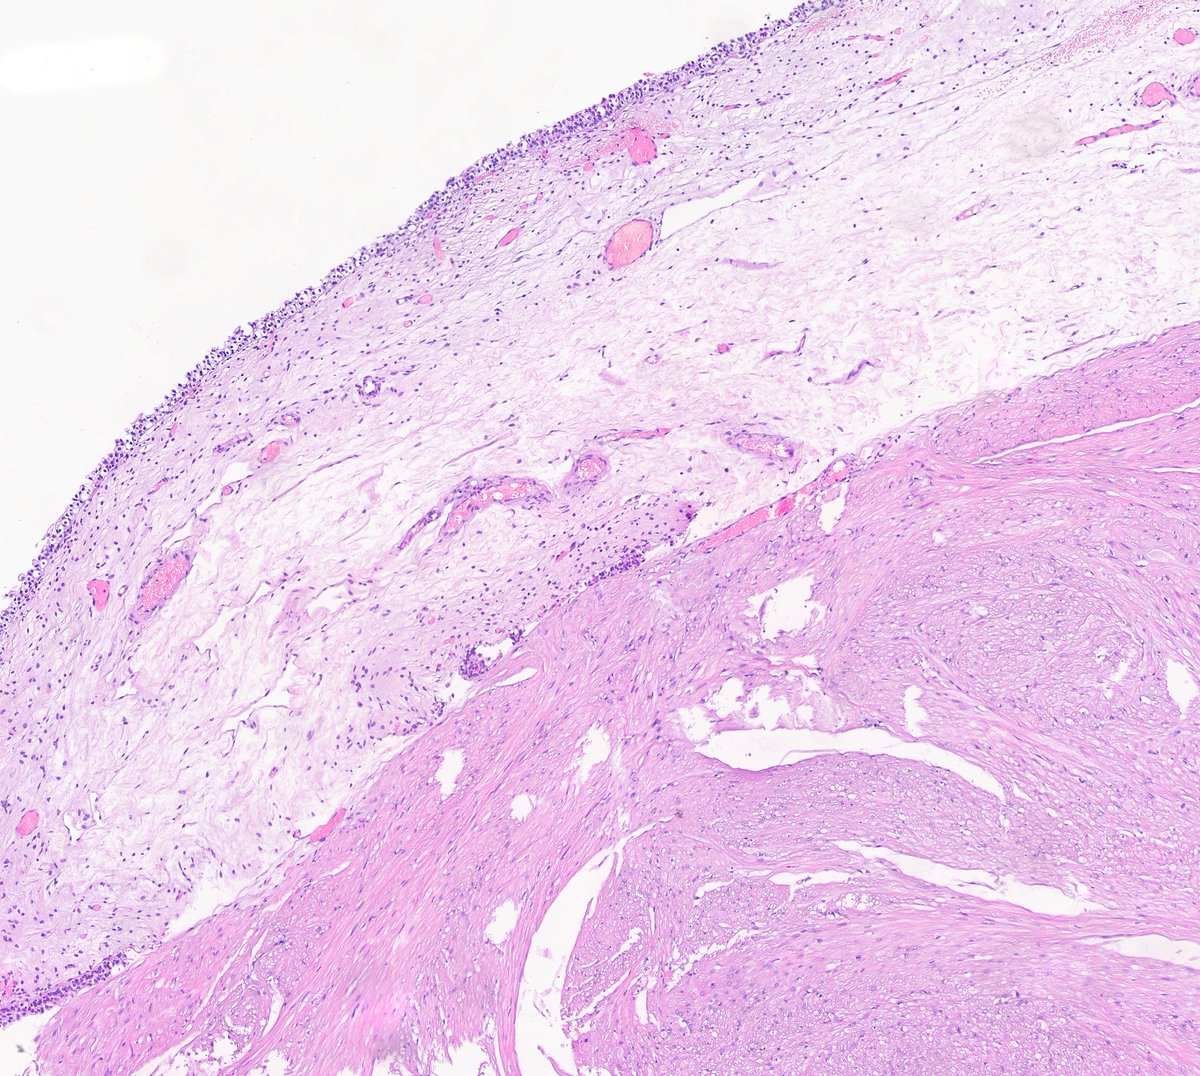

F40y,chronic cavitary pulmonary aspergillosis, atypical resection of the low lobe of the lung.

several cavities with a fungal ball, granulation tissue, chronic inflamation, metaplastic squamous epithelium, calcium oxalate crystals